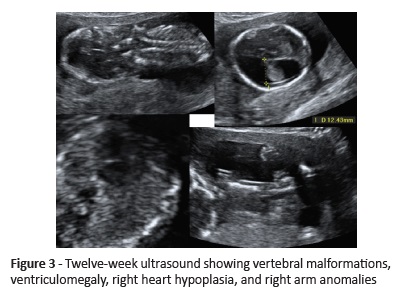

A nullipara woman with no relevant personal or family medical history was referred to our Hospital to perform first-trimester aneuploidy screening. She presented with a single fetus of 12 weeks and three days with 4.2-mm NT (> 95 percentile) associated with ventriculomegaly, cystic hygroma, abnormal cervical spine, right heart hypoplasia, ulnar deviation of the right hand, and left clubfoot (Figure 3).

On the other hand, in Case 2 the first trimester ultrasound allowed to identify three typical features of the condition: cardiac anomaly and vertebral and limb defects.